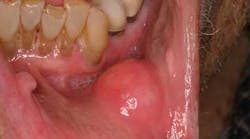

The lips: The lips should be evaluated with the mouth open and closed, noting any abnormalities in symmetry, contour, color, or texture. Attention to the vermilion border of the lower lip is warranted as this is a prime site for oral cancers. First, revert the lower lip and inspect the inner surface. The labial mucosa should be smooth and uniform in color. Notice the frenum of the lip in the midline. Note any signs of smokeless tobacco use (ulcers, red or white discolorations, texture variations) on the labial mucosa. With the lip still retracted, one can also inspect the gingivolabial sulcus, the gingival mucosa, and the teeth. Next, palpate the lip with your thumb and index finger, noting any firm or nodular submucosal areas (figure 1). Repeat these steps for the upper lip.

Figure 1